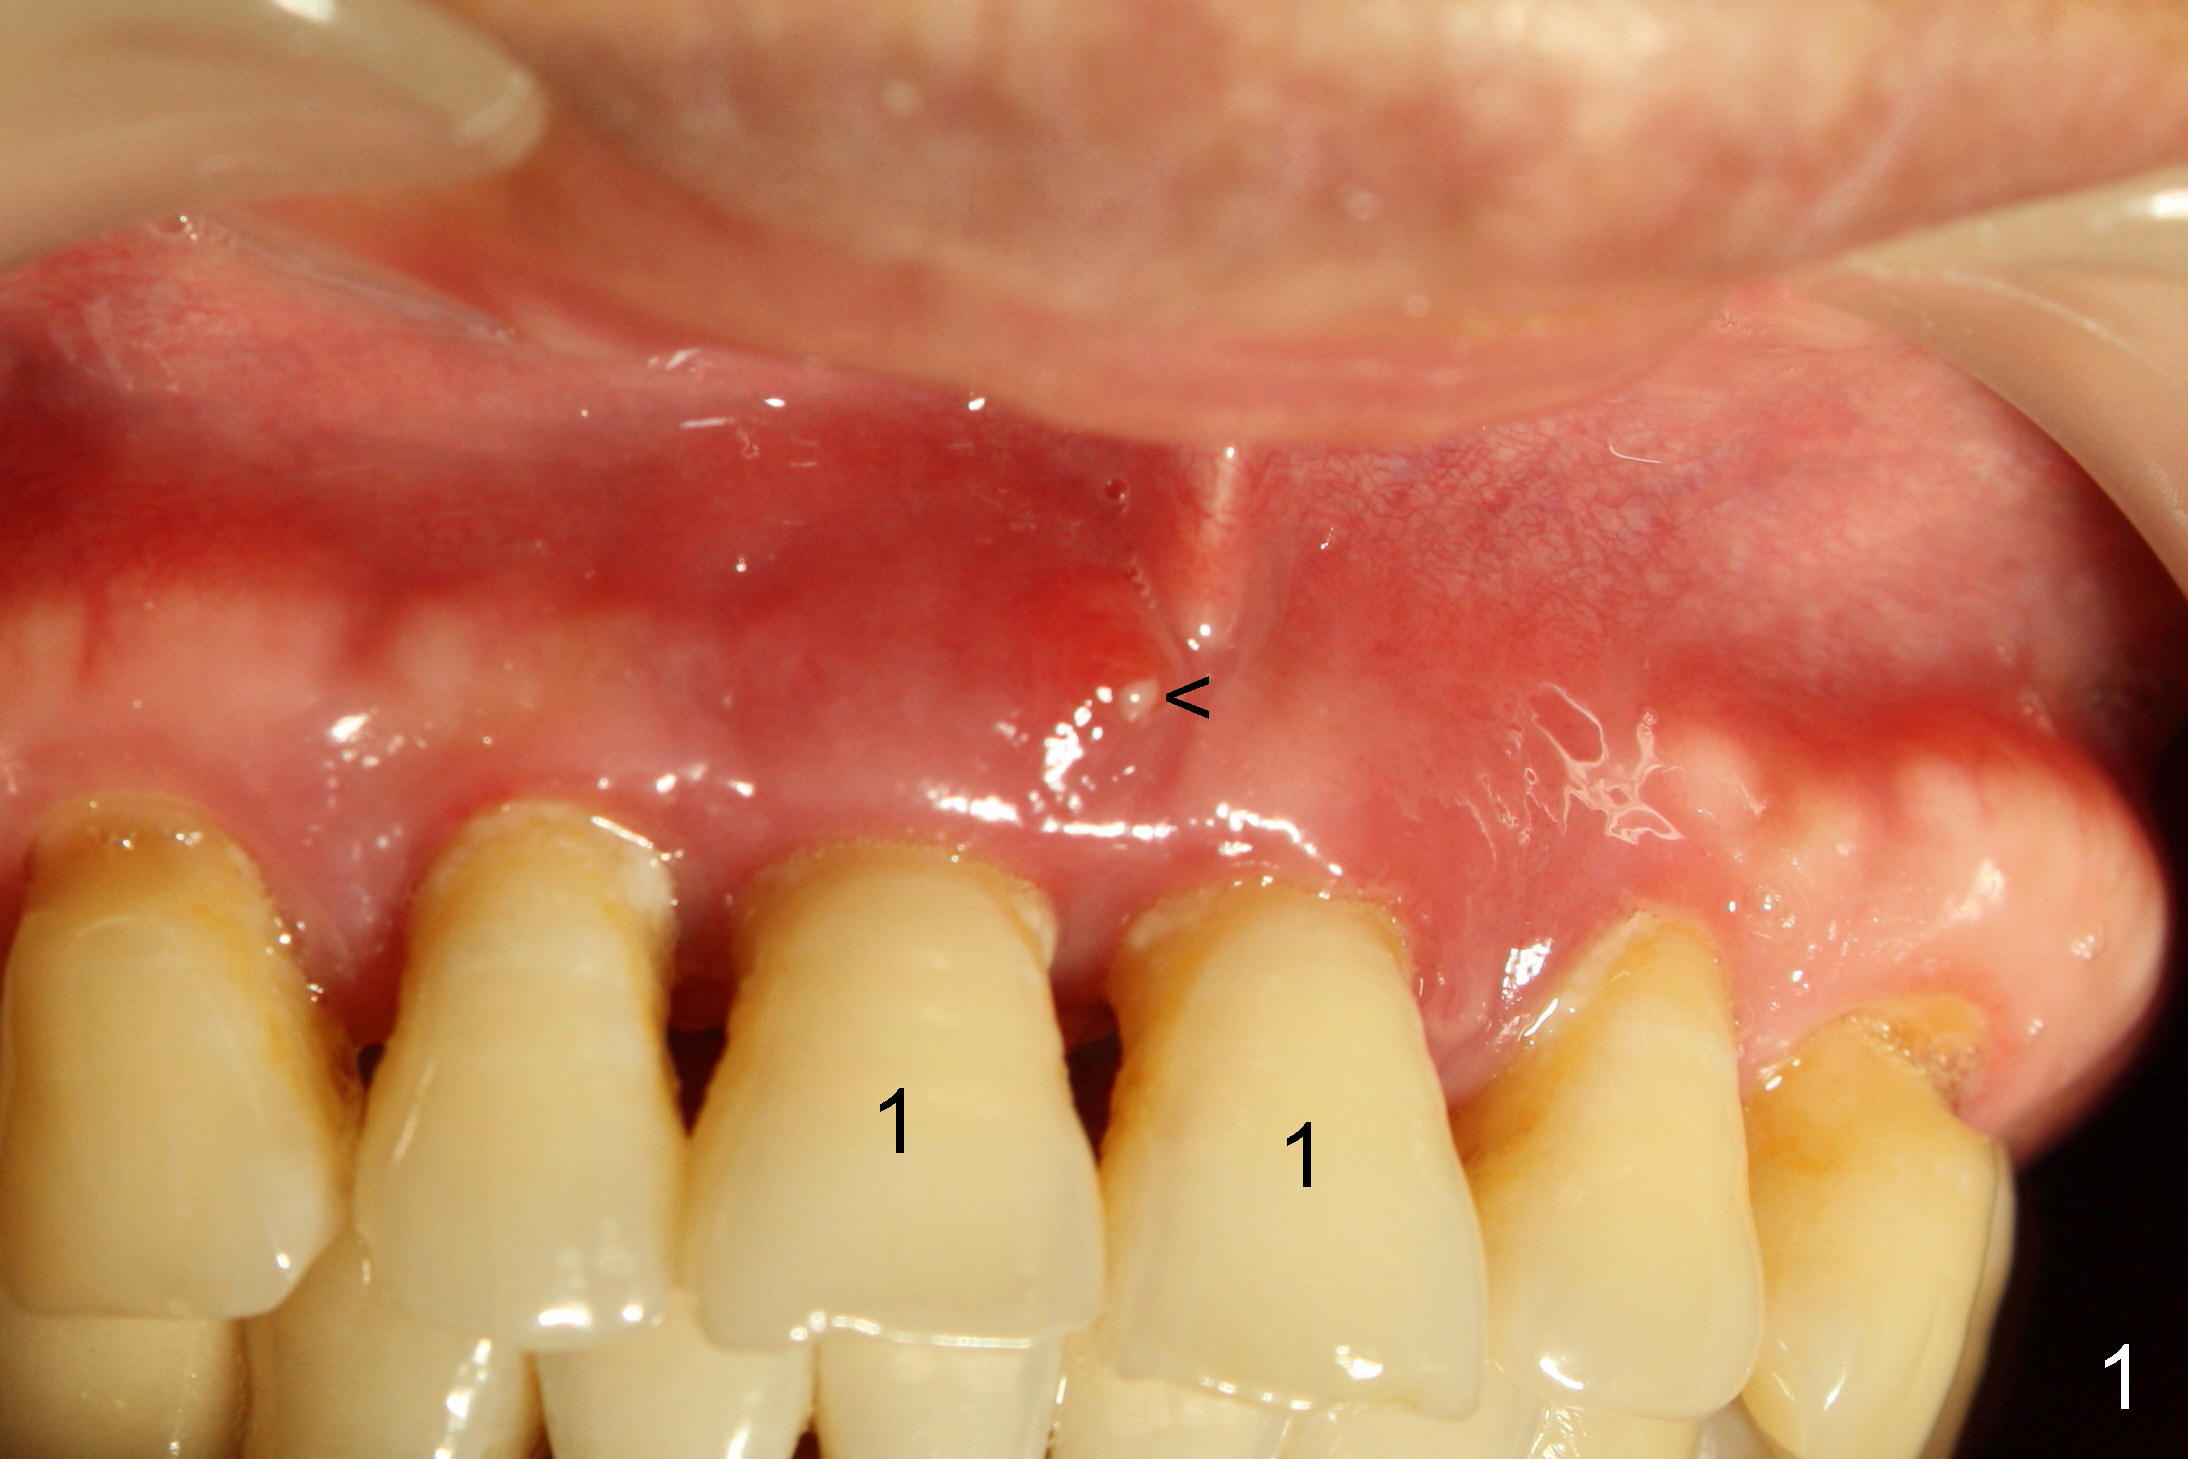

Nasal Lift Associated with Incisor Immediate Implants

A 44-year-old man has advanced periodontitis (Fig.1,2). The infection resolves substantially 5 days post scaling & root planing (Fig.4,5). The two centrals have severe bone loss (Fig.3) and are going to be replaced by 5x20 mm implants (Fig.6).